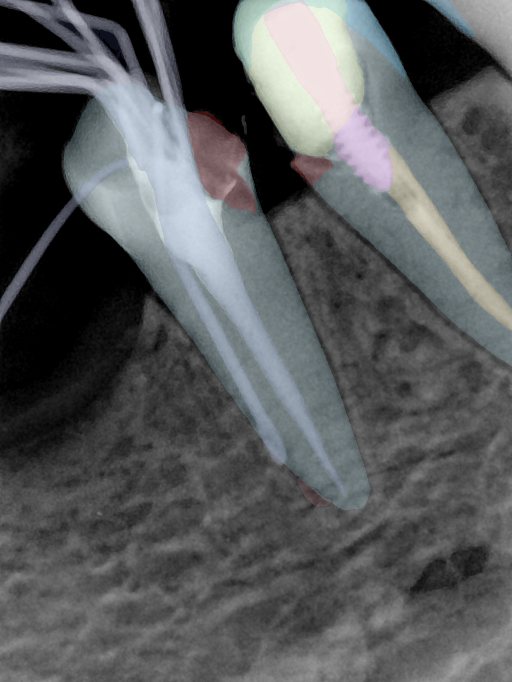

CR/DR 牙齿分割阶段记录

当前进展

- 完成了 CR/DR 牙齿相关分割训练

- 当前结果已经达到阶段预期,但仍有细节问题需要继续处理

相关测试

遇到的问题

- 训练过程中出现过 mask 下移问题

- 部分结果会出现 box 填充异常

- mask 边缘仍然有比较明显的锯齿感

参考

第二版算法问题测试

第三版算法分辨率效果比较

| 编号 | 原图 | 第一版 | 第二版 | 第三版 1216x1600 | 第三版 768x1024 | 第三版 1120x1120 |